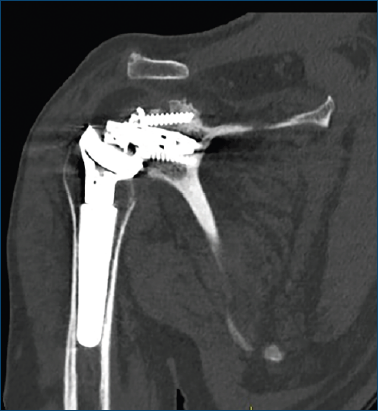

Al follow-up postoperatorio a 1 mese, le radiografie hanno mostrato la mobilizzazione del metal-back baseplate glenoideo (Fig. 1) e il paziente ha riferito dolore senza una causa apparente. Come raccomandato dalla letteratura, si è optato per una revisione della RSA utilizzando una ulteriore RSA 6,7.

Figura 1. TC della spalla destra, coronale. Mobilizzazione del metal-back glenoideo.